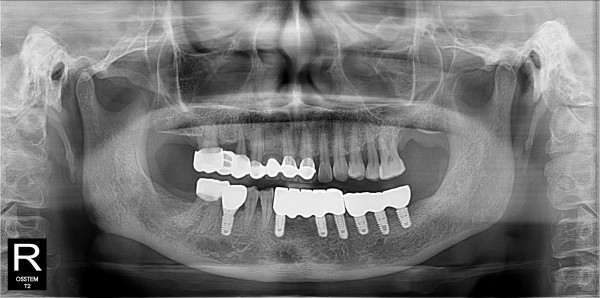

네비게이션 임플란트 최고관리자 0건 23-11-07 18:40 본문 하악 틀니에서 네이게이션 임플란트 목록 다음글네비게이션 임플란트 23.11.07 댓글목록 0 댓글목록 등록된 댓글이 없습니다.